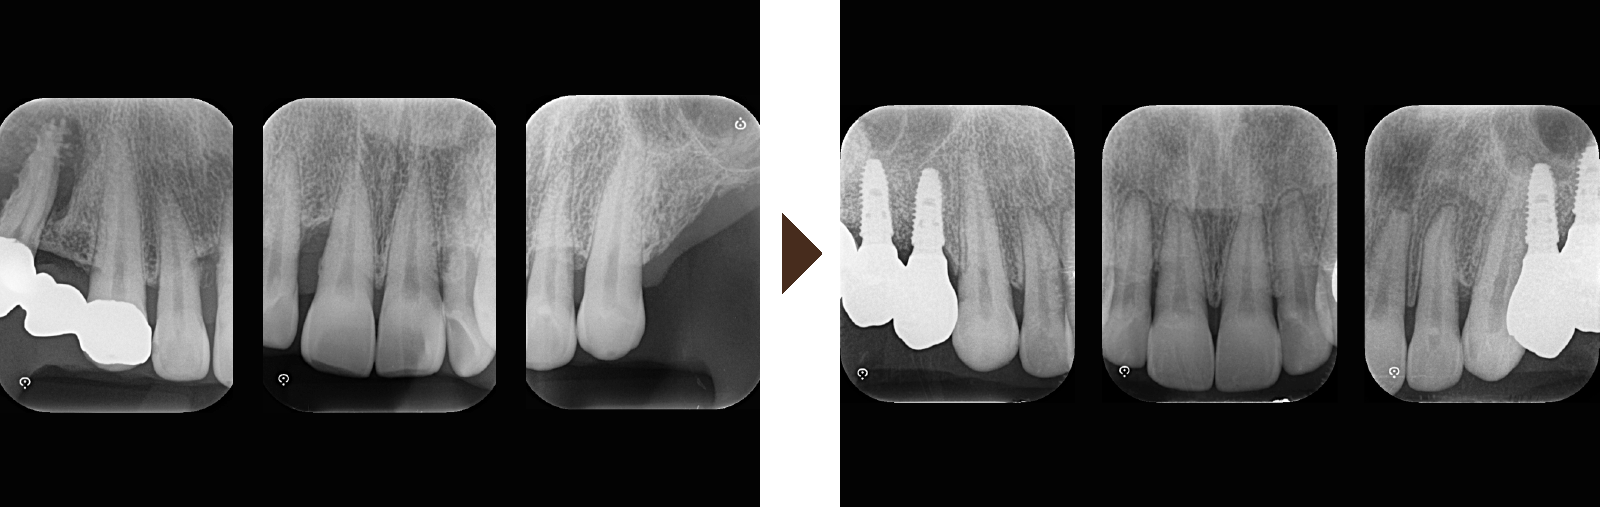

歯周組織再生療法は施術の難易度が高く、ほとんどの歯科では扱っていない内容です。

専門医資格を持つ医師が歯周組織再生治療を手がけるので、安心して治療を受けていただけます。